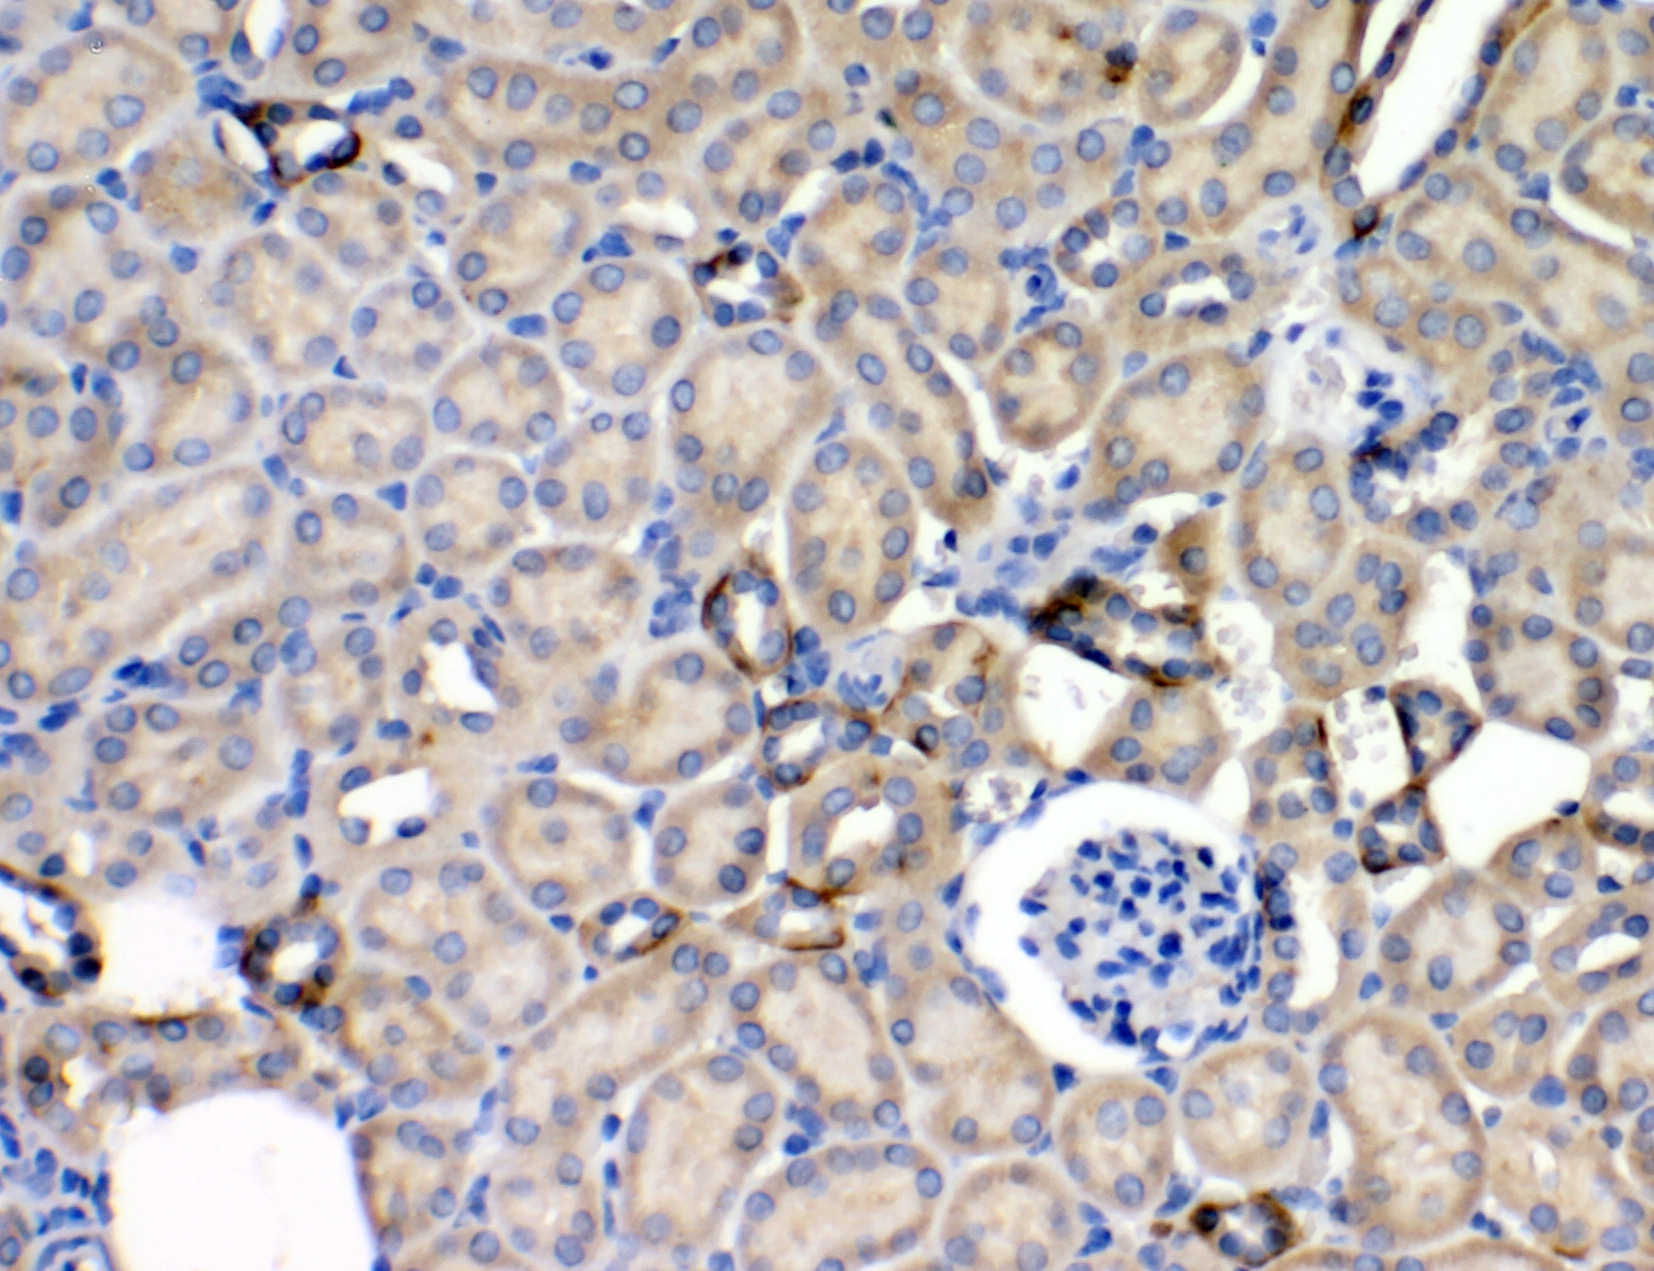

IHC analysis of LEPR using anti-LEPR antibody (BA1234).

LEPR was detected in a paraffin-embedded section of human kidney tissue. The tissue section was incubated with rabbit anti-LEPR Antibody (BA1234) at a dilution of 1:200 and developed using HRP Conjugated Rabbit IgG Super Vision Assay Kit (Catalog # SV0002) with DAB (Catalog # AR1027) as the chromogen.